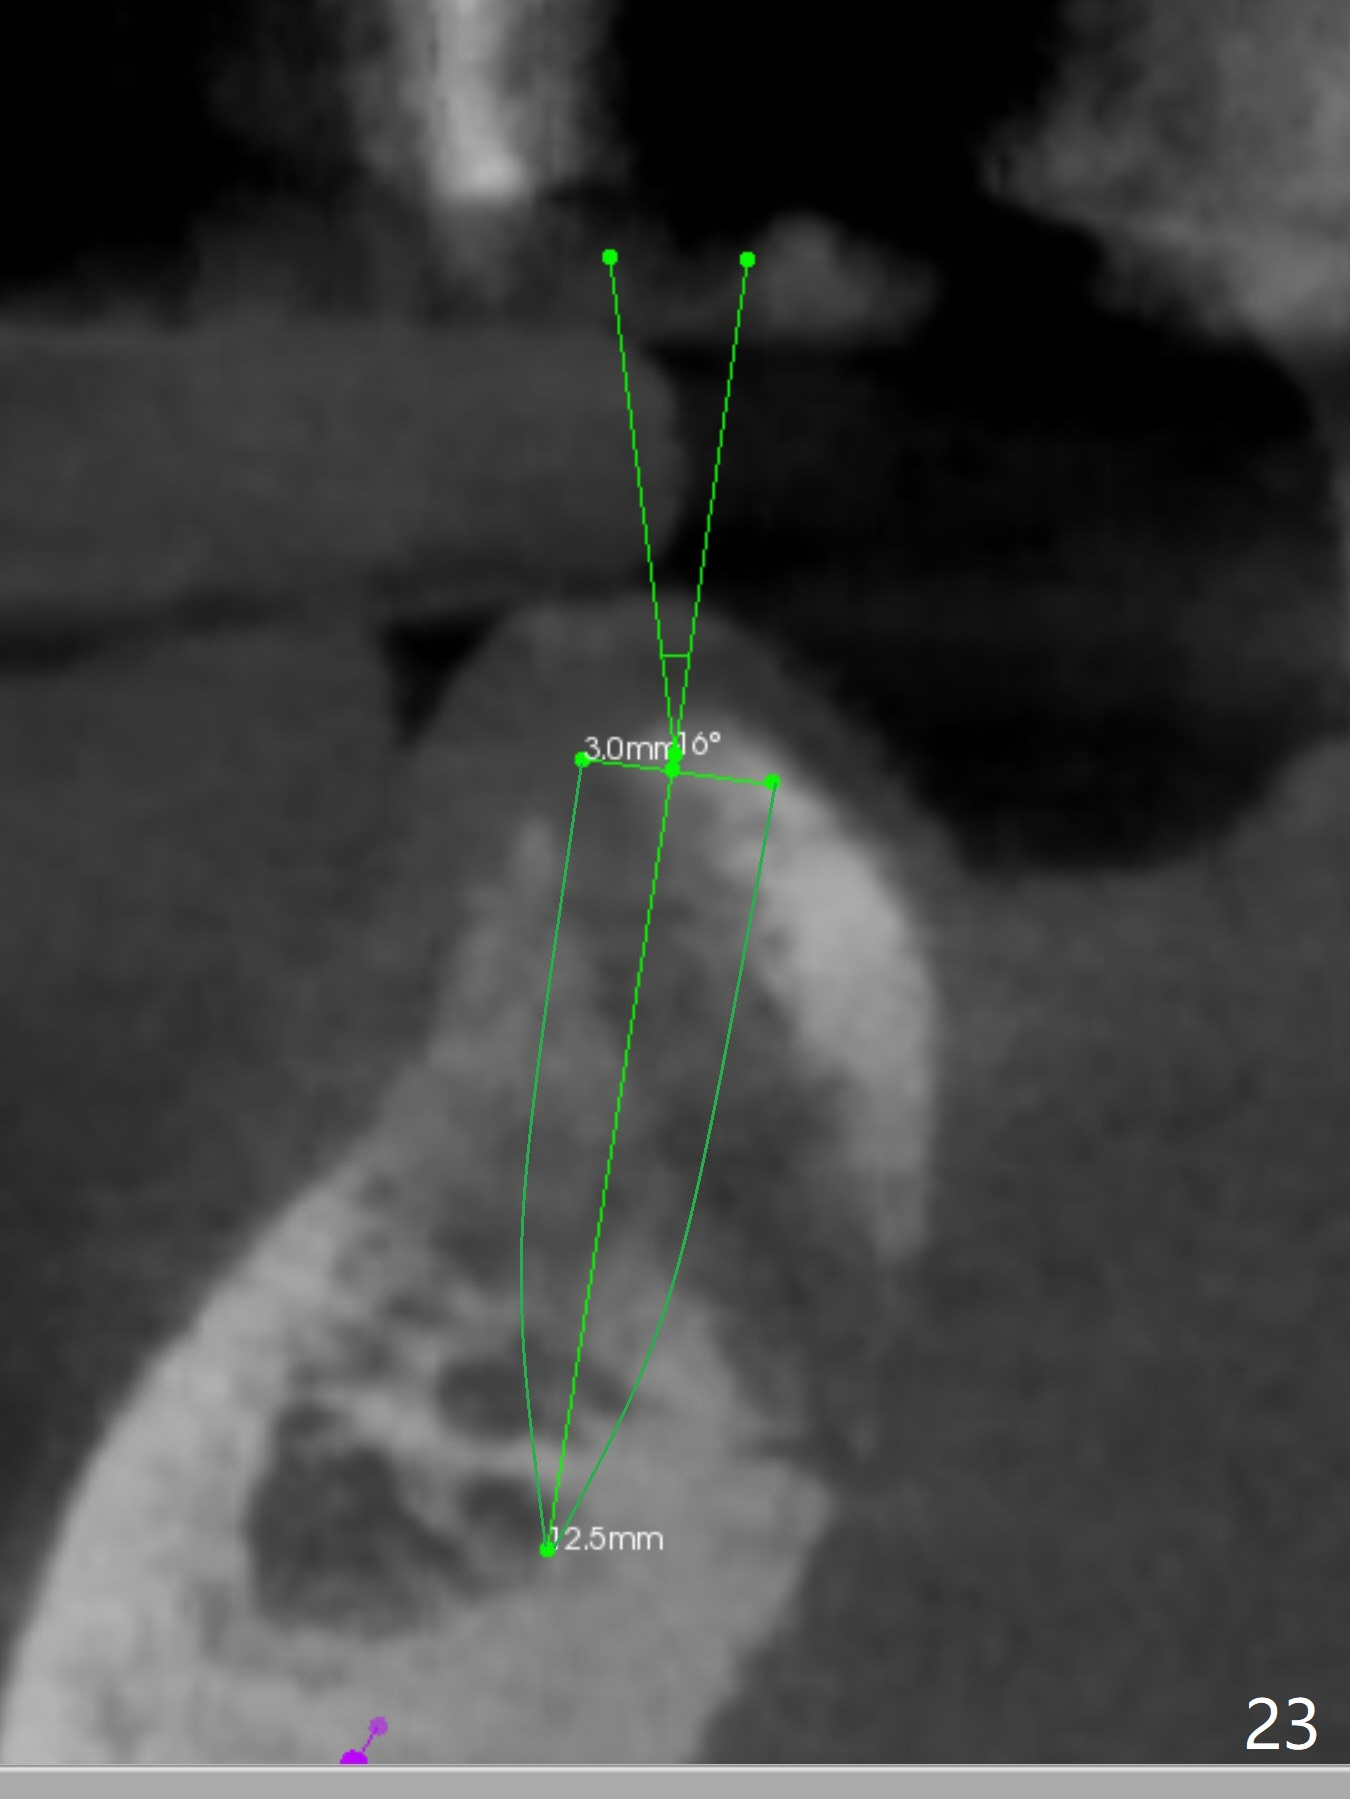

In fact the apex of the lateral incisor is also in the center of the alveolus (Fig.9 *). Osteotomy established in the lingual slope for a long distance (Fig.10,11) will perforate the lingual plate. The correct method of osteotomy is to set up in the middle of the socket and along the long axis of the alveolus with 2 fingers holding the alveolus (Fig.12 (2 circles)). The problem for this case is to use the lower RPD as a guide. With the RPD in place, the tactile sensation is lost.

When the bone height seems to be limited in the lower anterior region, use short implants. CT is retaken nearly 2 months post implant removal (Fig.22,23 (O: opposing tooth)). It seems possible to re-place a smallest 2-piece implant where the bone is relatively wide (Fig.22) and a 3-mm 15 degree angled 1-piece implant where the bone is narrow (Fig.23) by simply changing trajectory. New implants are placed nearly 3 months post implant removal (Fig.24,25). In fact the site of #27 re-perforates; a shorter implant is placed with bone graft apically. Immediate provisional is fabricated so that the clasp is not irritating. There is moderate edema and pain lingual to #27 site postop. Augmentin is taken for 3 weeks with alleviation of the symptoms. The implant at #27 is loose 1 month postop and removed.